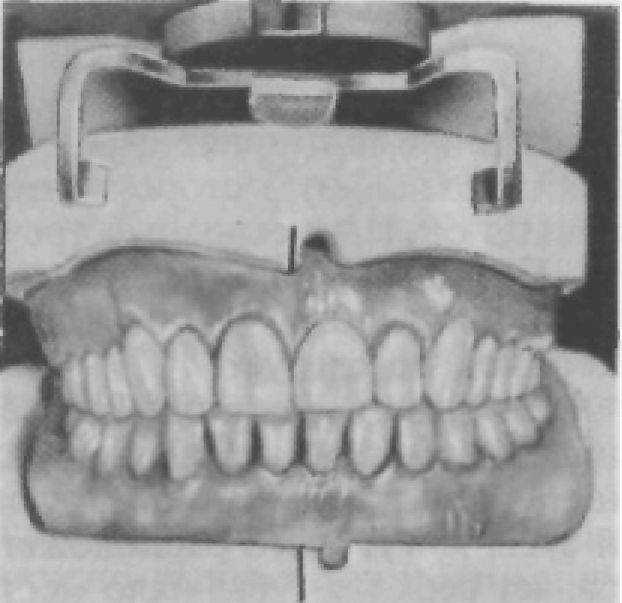

В зависимости от постановки передних зубов верхнего ряда в вертикальной плоскости может значительно меняться лицо человека (рис. 219). Пациентам предлагают произвести речевую пробу, при которой расстояние между передними зубами верхней и нижней челюстей должно быть приблизительно 5 мм.

Рис. 219. Внешний вид в зависимости от постановки передних зубов.